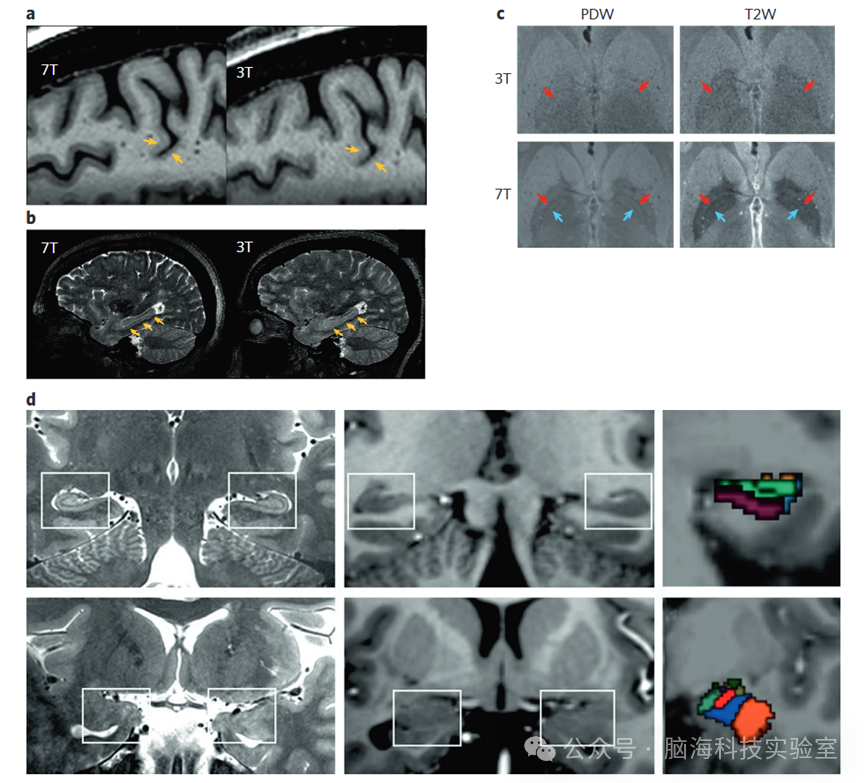

7T结构成像的优势来自多个方面。首先,更高的信噪比(SNR)能够实现高空间分辨率,以便精确分割解剖特征并计算结构指标,例如灰质体积和皮层厚度。通过采集更小、更各向同性的体素,这些结构指标的准确性得到提高;7T提供的体素尺寸减小能够通过减少部分容积效应的影响来降低局部体积估计的偏差。其次,与3T相比,7T的磁场强度增加会产生更长的T1弛豫时间,从而增强组织类型之间的对比度,并实现对解剖学上不同的脑区和核团的更准确分割。第三,无论是基于对比度的还是定量结构测量的磁共振序列(如MP2RAGE序列),都更容易应用于7T协议,因为它们受益于超高场强下的高信噪比和对比度。以MP2RAGE为例,它在不同的反转时间(通常包括T1加权和质子密度加权图像)采集两个梯度回波图像,并将它们结合起来生成定量的T1图和基于对比度的均匀(UNI)图像,该图像具有更均匀的强度和更优越的灰白质对比度。这些改进使得解剖定位和分割得到增强(例如,图2a--c),对皮层形态的评估更加精确,偏差减少,从而提高了测试-重测的可靠性,并有助于追踪纵向变化,这对于临床研究通常是至关重要的。7T已显示出对临床人群灰质厚度变化的敏感性,例如,识别首发精神病患者中广泛的皮层厚度减少。机器学习方法也显示出在7T下基于灰质和白质测量对患者和对照组进行分类的能力优于3T,从而将实现与3T相当的预测性所需的患者数量减少了30%--50%。

7T结构成像还提供了更准确地研究小结构的机会,特别是那些具有已知临床相关性的深部和皮层下脑区。一个典型例子是对海马体的增强表征,其中可以在亚毫米结构扫描中准确识别亚区,并采用自动分割方法(图2d)。海马体是重度抑郁症和精神分裂症病理生理学的核心区域,尤其是在精神病早期阶段,体积变化尤为明显。然而,大多数3T研究将海马体视为单一结构,或者仅限于长轴(前后轴)分析。7T的分割验证了精神分裂症中的体积变化,表明CA4/DG是这些减少的主要来源,并与5-羟色胺(5HT1A和5-HT4)受体的改变有关。此外,还有研究发现了海马体解剖学上不同的亚区与临床的相关性,例如,将抑郁症患者的体积减少定位于CA2/3,将重度抑郁症对电休克治疗(ECT)的反应定位于齿状回,以及识别与精神病风险相关的心理社会因素(如一生中的压力)的差异性反应。在具有解剖学和功能上不同的亚区的其他皮层下区域中,也取得了类似的解剖学划分的进展。与3T相比,7T对皮层下核团(包括黑质和内外苍白球)的分割提高了可靠性,这使得能够创建高分辨率的解剖图谱。对基底神经节核团的识别,包括苍白球亚段,对于通过改善解剖定位来指导深部脑刺激靶点具有重要意义,这可能会改善临床结果。在杏仁核中,3T研究通常能够识别基底外侧和中央内侧亚区,但7T的高分辨率结构MRI可能支持绘制九个不同的亚核。小结构映射已被应用于临床队列的数据,特别是在重度抑郁症的背景下,显示出临床严重程度与杏仁核亚核体积、缰核和岛叶亚区的关联。

图2 不同大脑区域和模式的7 T与3 T解剖图像的比较